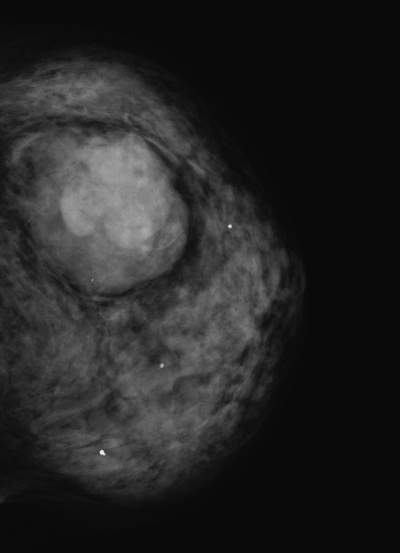

74歳の女性。左乳房のしこりを主訴に来院した。30 年前に左乳房にゴルフボール大のしこりがあるのに気付いていたが、大きさに変化がないためそのままにしていた。先日、入浴時にしこりの増大に気付き心配になり受診した。乳房に色調の変化やひきつれを認めない。表面平滑で弾性硬、可動性良好な径3cmの腫瘤を触知 する。腋窩リンパ節を触知しない。左乳房のマンモグラムと胸部CTとを示す。

考えられる診断はどれか。

e. 乳腺葉状腫瘍